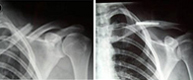

Las fracturas de clavícula representan del 10 al 16% de todas las fracturas de nuestro esqueleto y son las fracturas más frecuentes de la infancia. Afectan fundamentalmente a su tercio medio (75%) y no suelen producirse por impacto directo sobre ella, sino, por una caída sobre el hombro, el cual transmitela fuerza deformante hacia la clavícula produciendo su fractura.

Este tipo de lesión es característico, pues, de aquellos deportes que pueden provocar impactos violentos sobre el hombro como caídas desde bicicleta, motocicleta, patín, skate o deportes de contacto como rugby, hockey hielo, futbol americano, etc.

Con la finalidad de una rápida incorporación a la actividad deportiva proponemos siempre que sea posible una intervención mínimamente invasiva con una estabilización rápida a través de una pequeñísima incisión que garantiza una menor probabilidad de complicaciones.